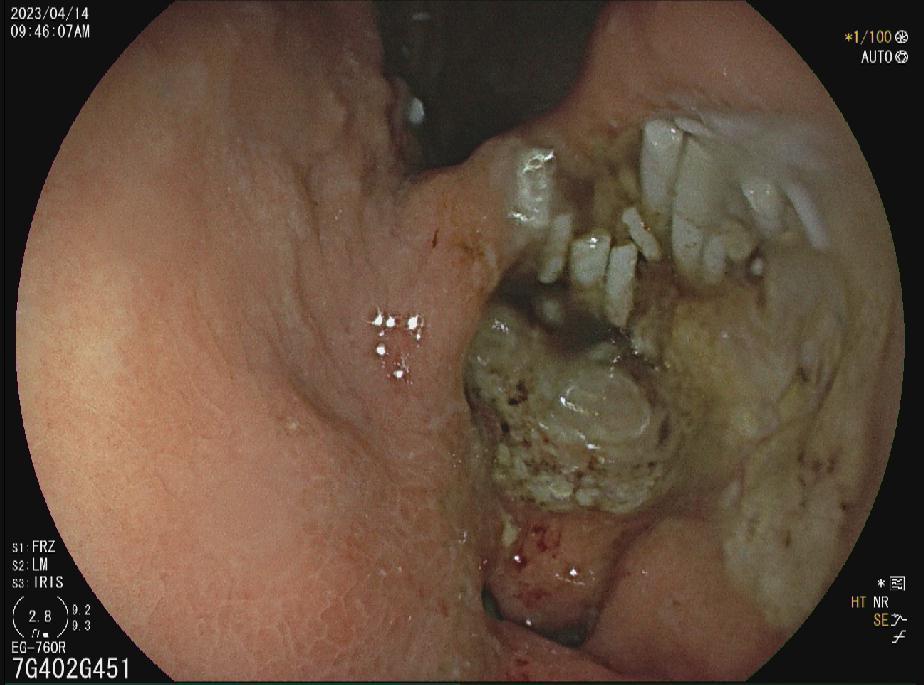

胃癌